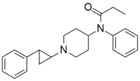

Chemical structures of various fentanyl analogues

trans-phenylcyclopropyl-norfentanyl | 1-(trans-2-Phenylcyclopropyl)-4-(N-propionylanilino)piperidine. | 102504-49-4 |

|